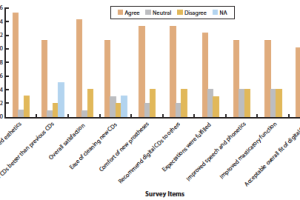

EVALUATION OF PATIENT EXPERIENCE AND SATISFACTION WITH CAD-CAM-FABRICATED COMPLETE DENTURES: RETROSPECTIVE SURVEY STUDY

Paola C. Saponaro, DDS, MS,a Burak Yilmaz, DDS, PhD,b William Johnston, PhD,c Reza H. Heshmati, DDS, MPH, MS,d and Edwin A. McGlumphy, DDS, MSe. Purpose. The purpose of this retrospective survey study was to assess patient preferences and satisfaction when treated with digitally fabricated CDs, by using a questionnaire.